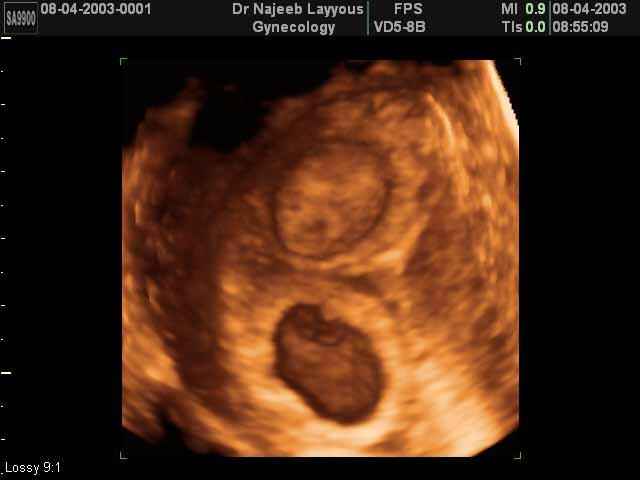

- 3D Photos échographie de grossesse multiple

3D Photos échographie de grossesse multiple : Jumeaux, triplés et quadruples| Dr N Layyous